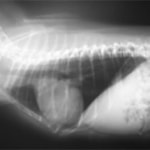

症例:【マルチーズ 12歳齢 去勢オス】

D:胸部レントゲン写真 正面像

E:胸部レントゲン写真 側面像

胸部レントゲン検査において重度の心拡大と肺水腫が認められた。超音波検査では、重度の僧帽弁閉鎖不全症、三尖弁閉鎖不全症、中程度の大動脈弁閉鎖不全症を合併していることが判明した。三尖弁逆流速度から肺高血圧症が示唆された。